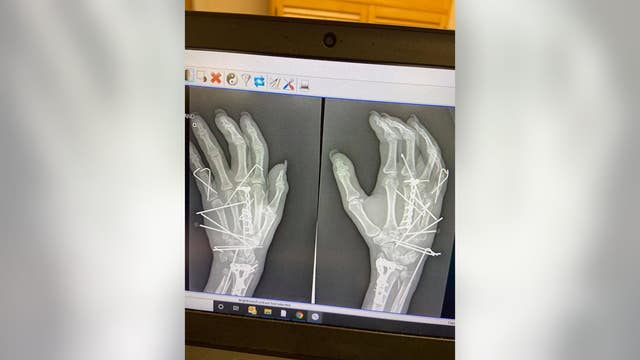

Mom warns against fireworks after one explodes and 'blew' her hand in half

Kristi Anema suffered a terrifying firework injury and is speaking out in hopes to promote safety ahead of the holiday weekend.